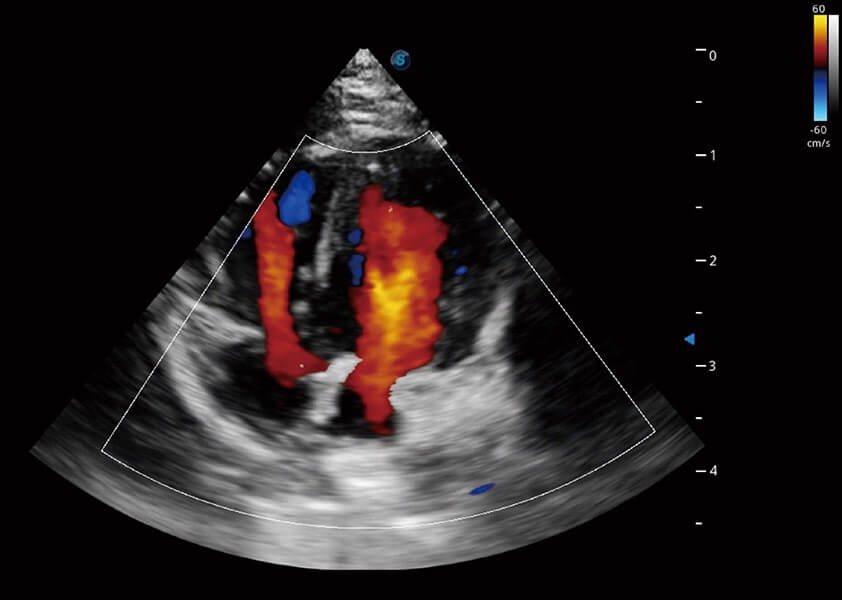

ProPet 60 作為一款高端臺式動物超聲設(shè)備,為動物醫(yī)生的日常診斷提供了一系列貼合動物臨床需求、解決臨床實際問題的高級成像功能。憑借全系列高清探頭,滿足醫(yī)生對腹部、心臟、生殖、淺表、肌骨等成像的所有需求,切實幫助您提升檢查效率,提高診斷信心。

動物是人類最親密的朋友和最值得信賴的伙伴。開立醫(yī)療也一直致力于探索動物專用的超聲影像解決方案。 全新推出的ProPet系列,是開立在動物超聲影像智能化、專業(yè)化、精準(zhǔn)化的一次跨越式革新。動物不能用言語來表述自己的不適,通過超聲影像,ProPet系列搭建了動物醫(yī)生與不同物種溝通的“橋梁”,為動物醫(yī)生注入了“治愈之力”。